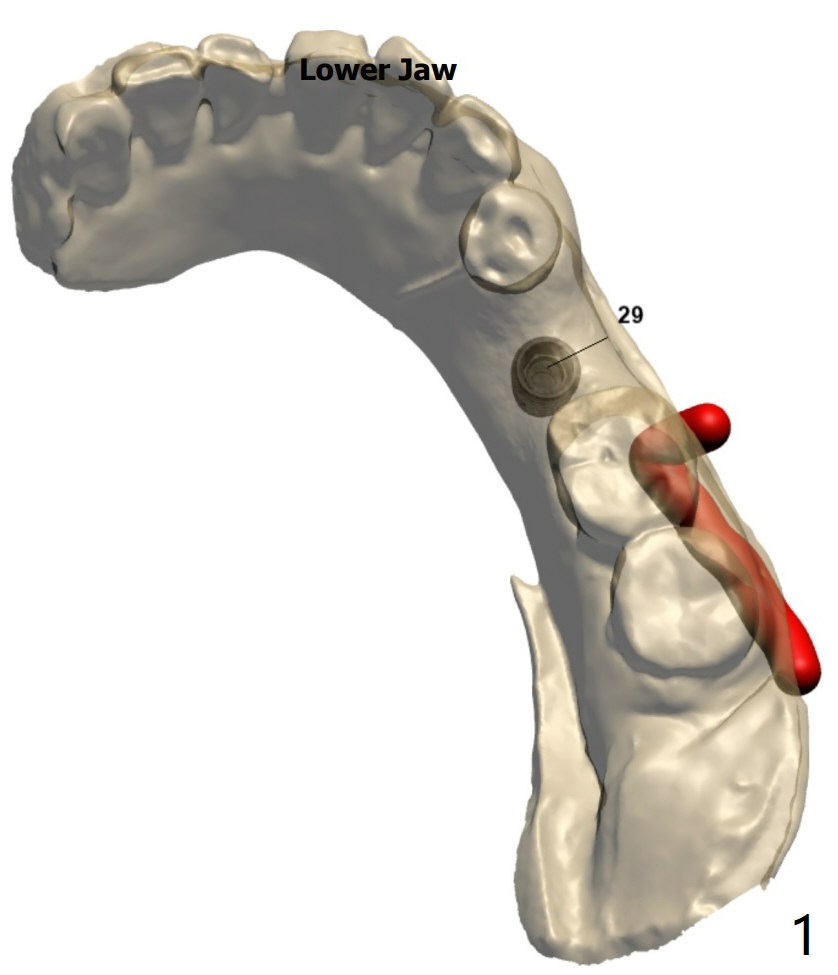

颊侧骨板缺失植骨后